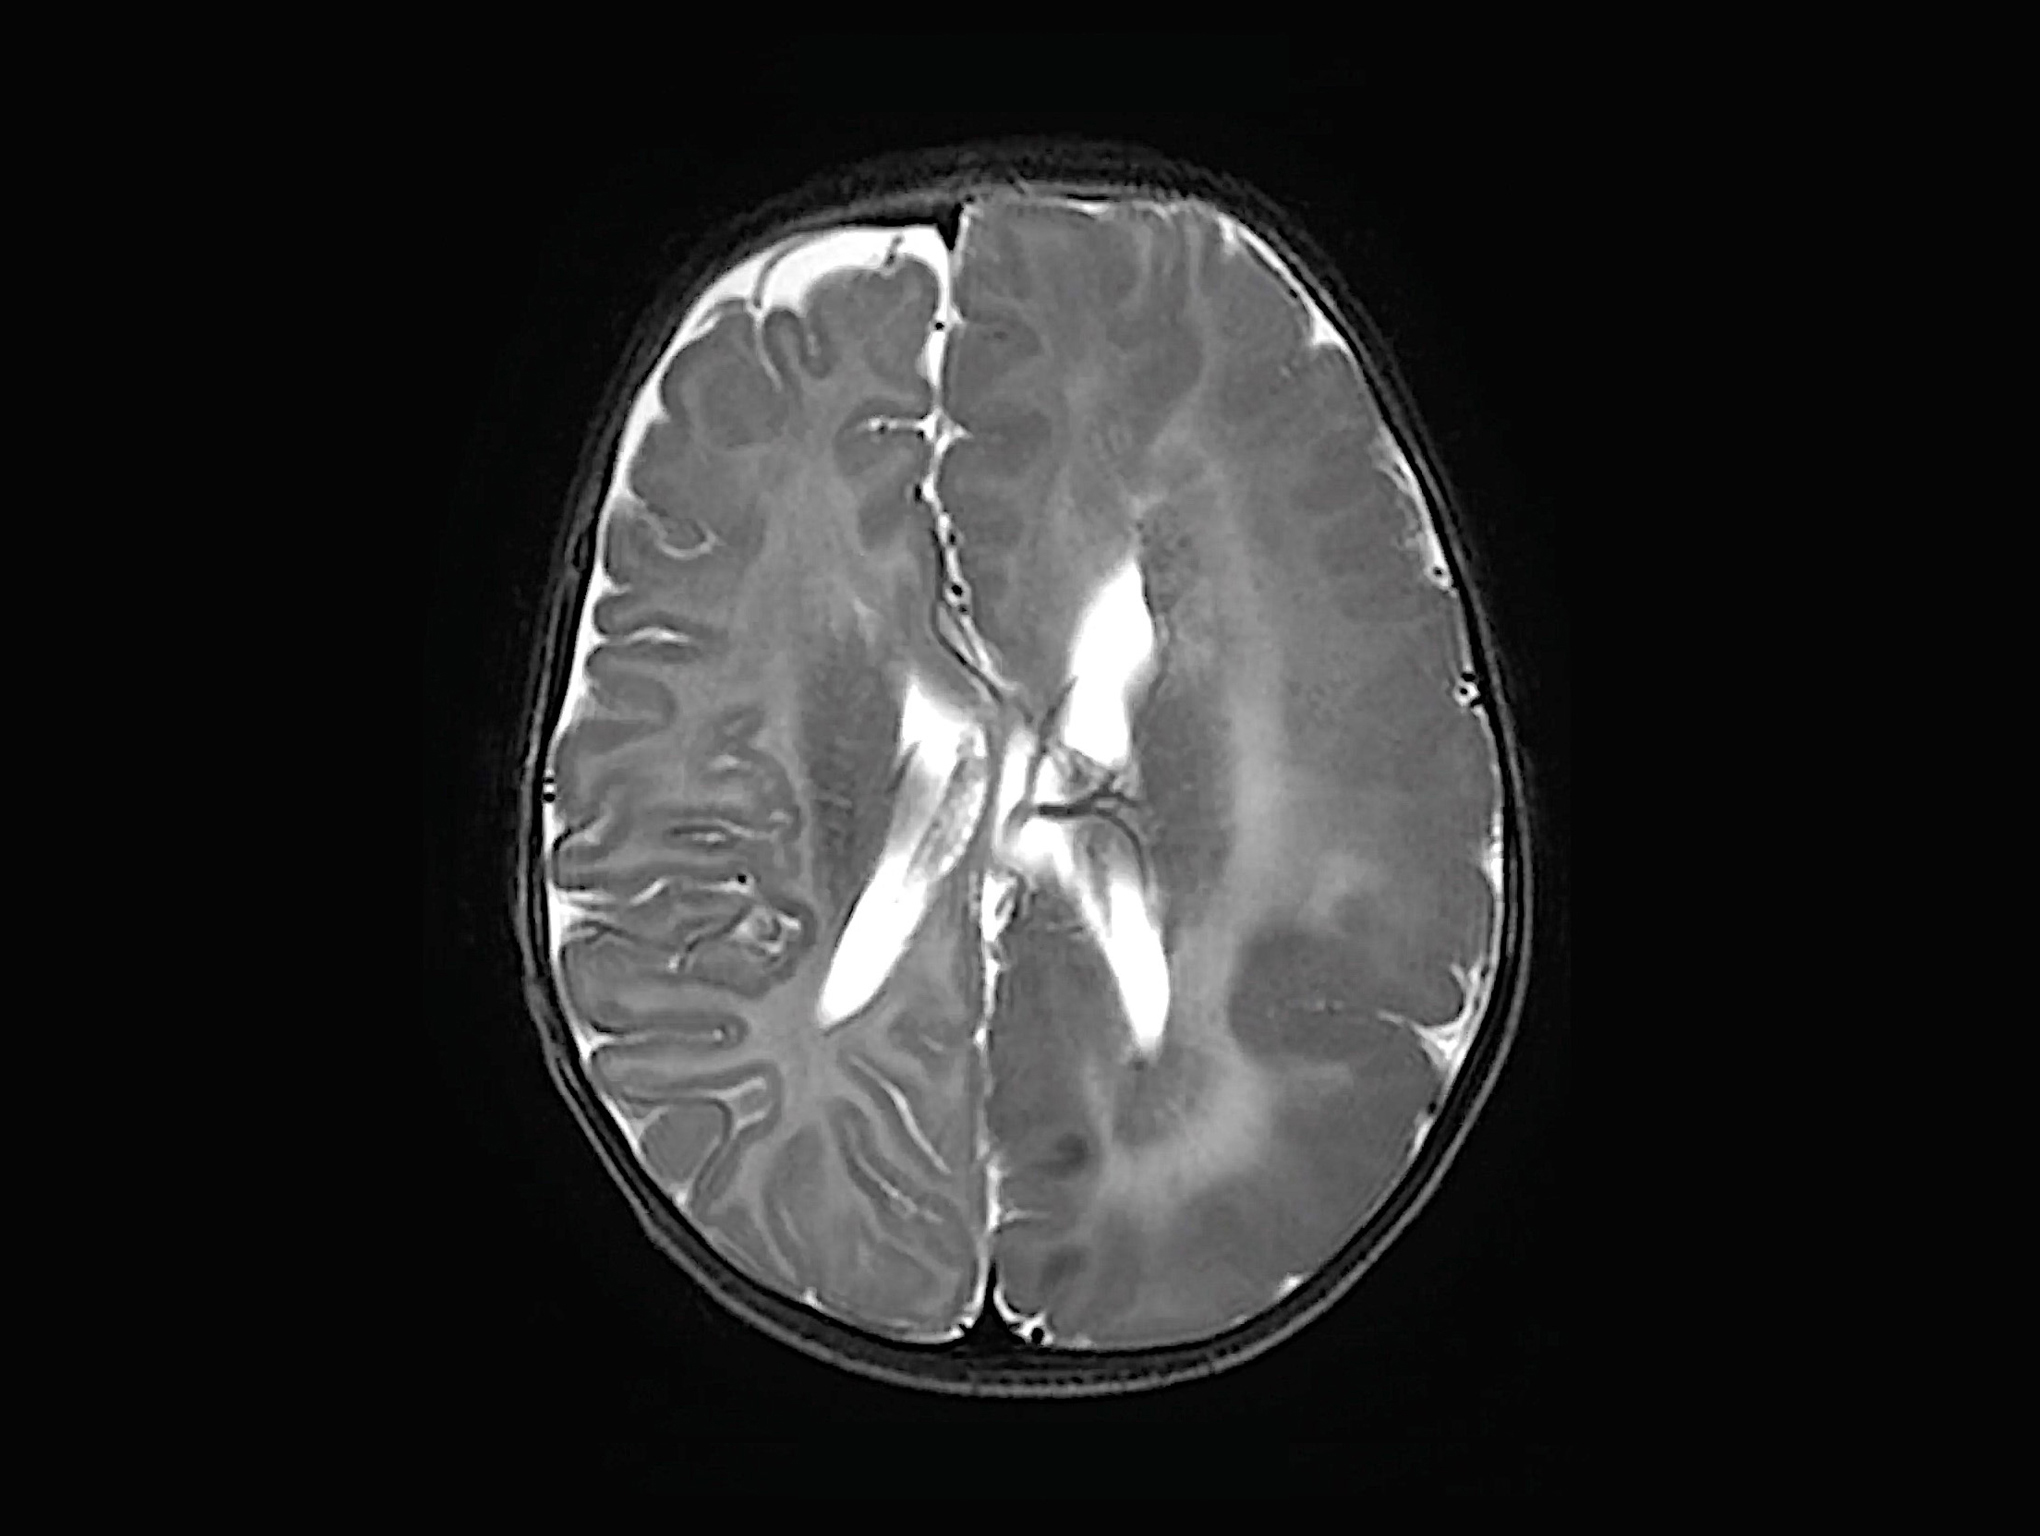

If the MRI scan were a piece of art rather than a medical image, the two halves of Maryam’s brain could have been rendered by entirely different artists. Her right brain hemisphere was like a pencil sketch, a work of realism; the brain folds looked clear and sharply defined, with the grey and white matter separated by distinct borders.

Her left brain hemisphere, however, was an abstract watercolour. The brain ridges looked puffy and haphazard, with the grey and white matter blurring together, as though too much water in the brush had caused the paint to bleed.

The left hemisphere of Maryam’s brain was also noticeably bigger. She was transferred to SickKids, where doctors diagnosed Maryam with hemimegalencephaly (HME), a rare birth defect where one side of the brain is abnormally large. The brain hemisphere’s function is so disturbed, and the neurons so disordered, that it is effectively capable of only one thing: causing seizures.